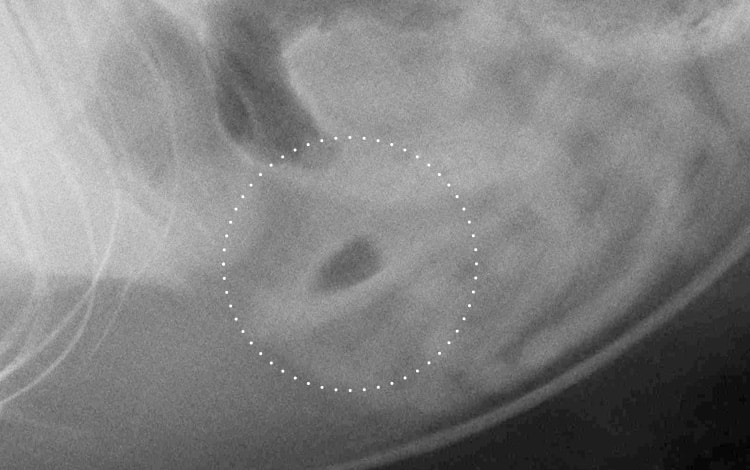

• Une radiographie simple du tube digestif du chat.

L’examen radiographique du tube digestif du chat peut révéler la présence visible du corps étranger si celui-ci est radioopaque (aiguille à coudre par exemple mais s’il s’agit d’une boule de poils, celle-ci ne se verra pas sur une radiographie simple) ou une forte constipation ou la présence de gaz importants…

• Des radiographies avec produit de contraste (ou transit baryté) du tube digestif du chat.

Plusieurs clichés radiographiques sont pris avant puis après ingestion par le chat d’un produit de contraste radioopaque (baryte). Cela permet de localiser la subocclusion et d’évaluer son intensité. Une anesthésie peut être nécessaire pour pratiquer cet examen.

1 • Radiographie mettant en évidence la présence d’un corps étranger dans l’intestin d’un chat.